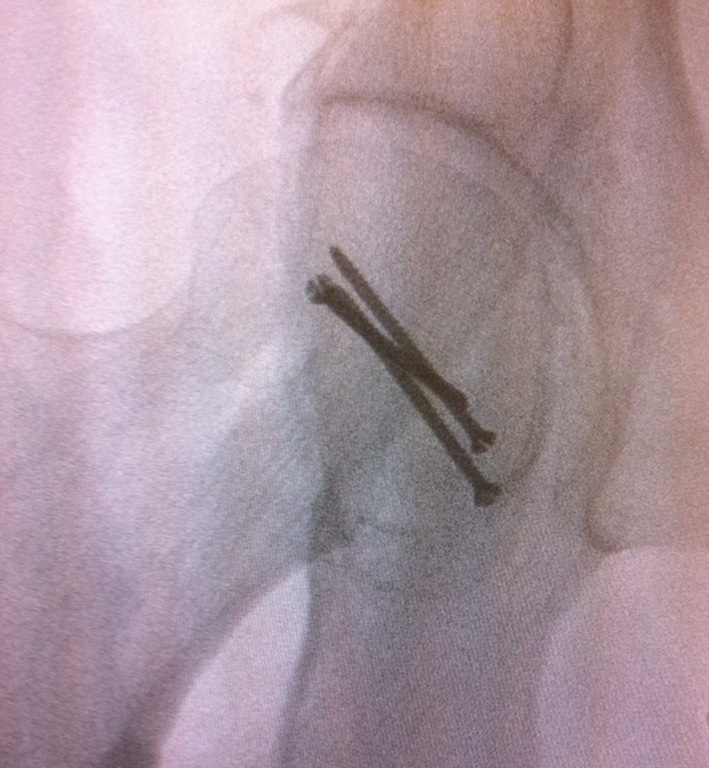

Type III

- anterolateral approach / Watson Jones

- ORIF NOF + fix/excise Pipkin fracture in young patient

- very high incidence AVN

- THR > 60